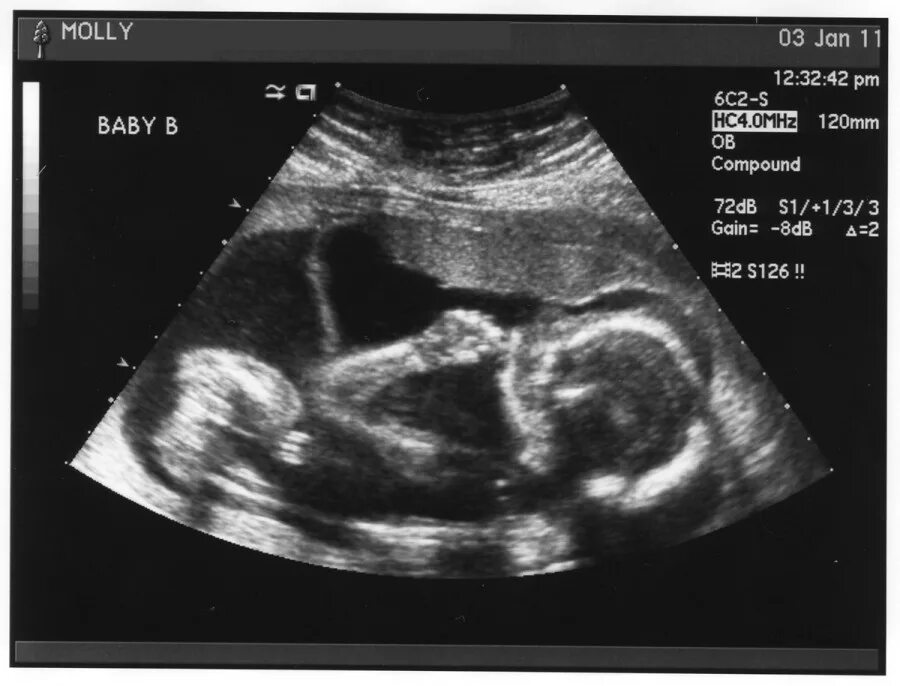

Беременность 12 недель ощущения в животе